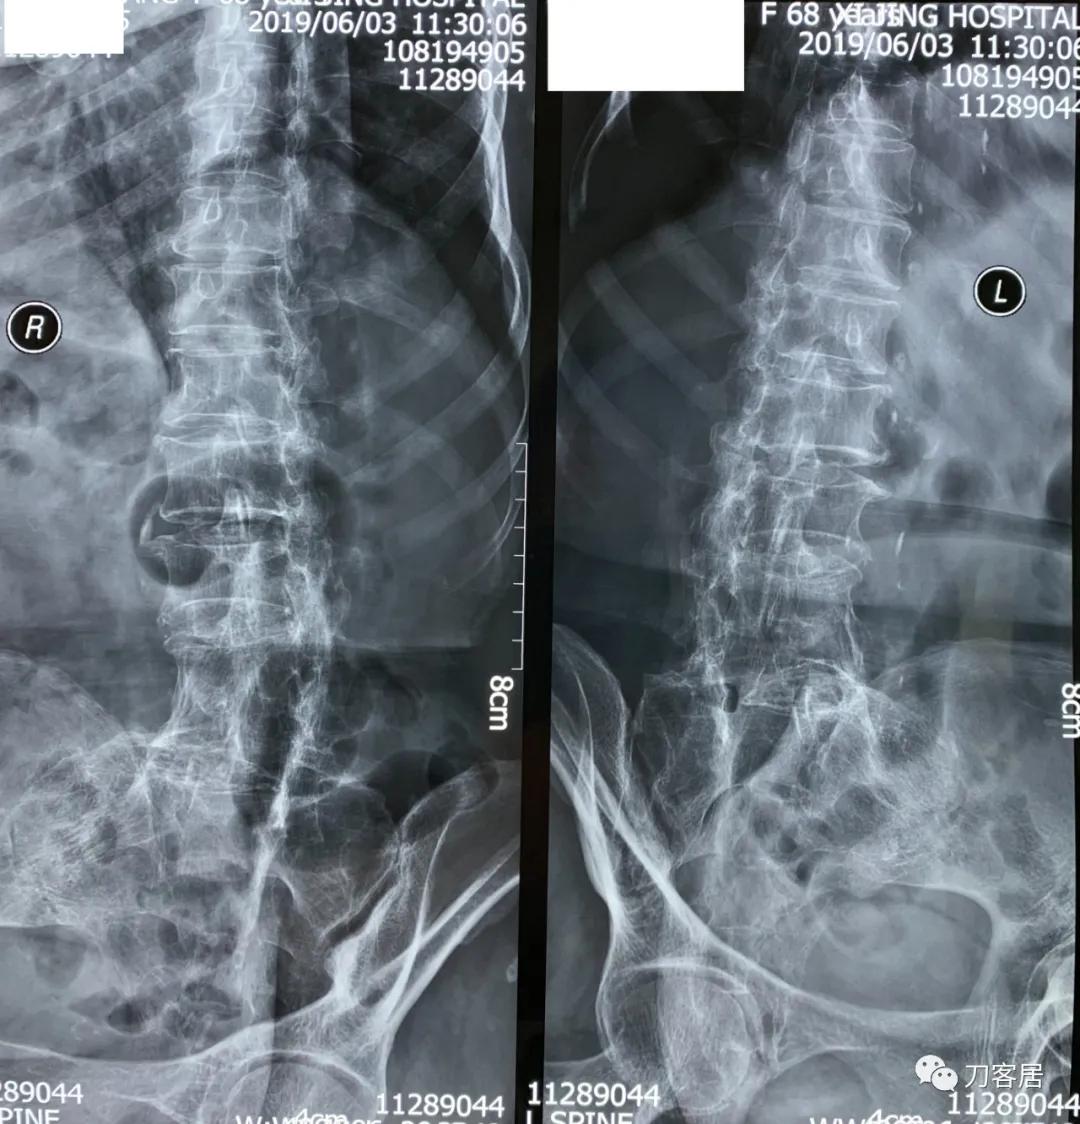

家属携带的影像学检查提示腰4-骶1病灶清除植骨融合术后改变,骨质疏松严重,未见椎旁脓肿以及结核病灶复发破坏。血沉、C反应蛋白化验检查结果正常。

诊断:腰4-骶1病灶清除植骨融合术后,严重骨质疏松症。

图3. 20190603西京医院腰椎双斜位X线片